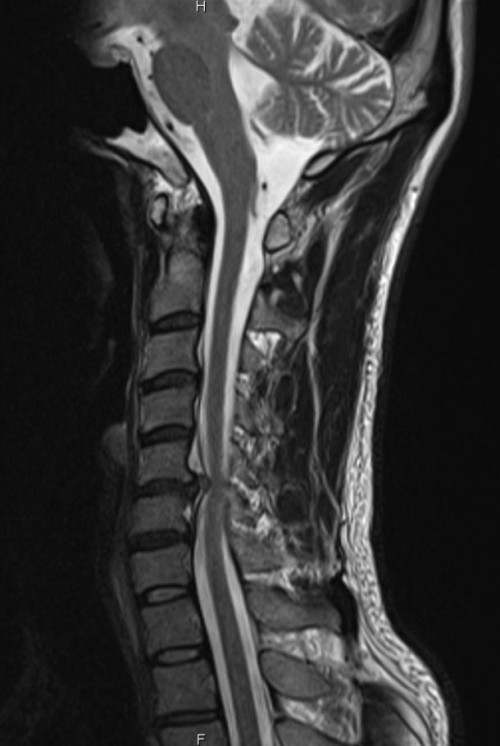

I’ve looked at his MRI scan and it looks like exactly like pictures below: